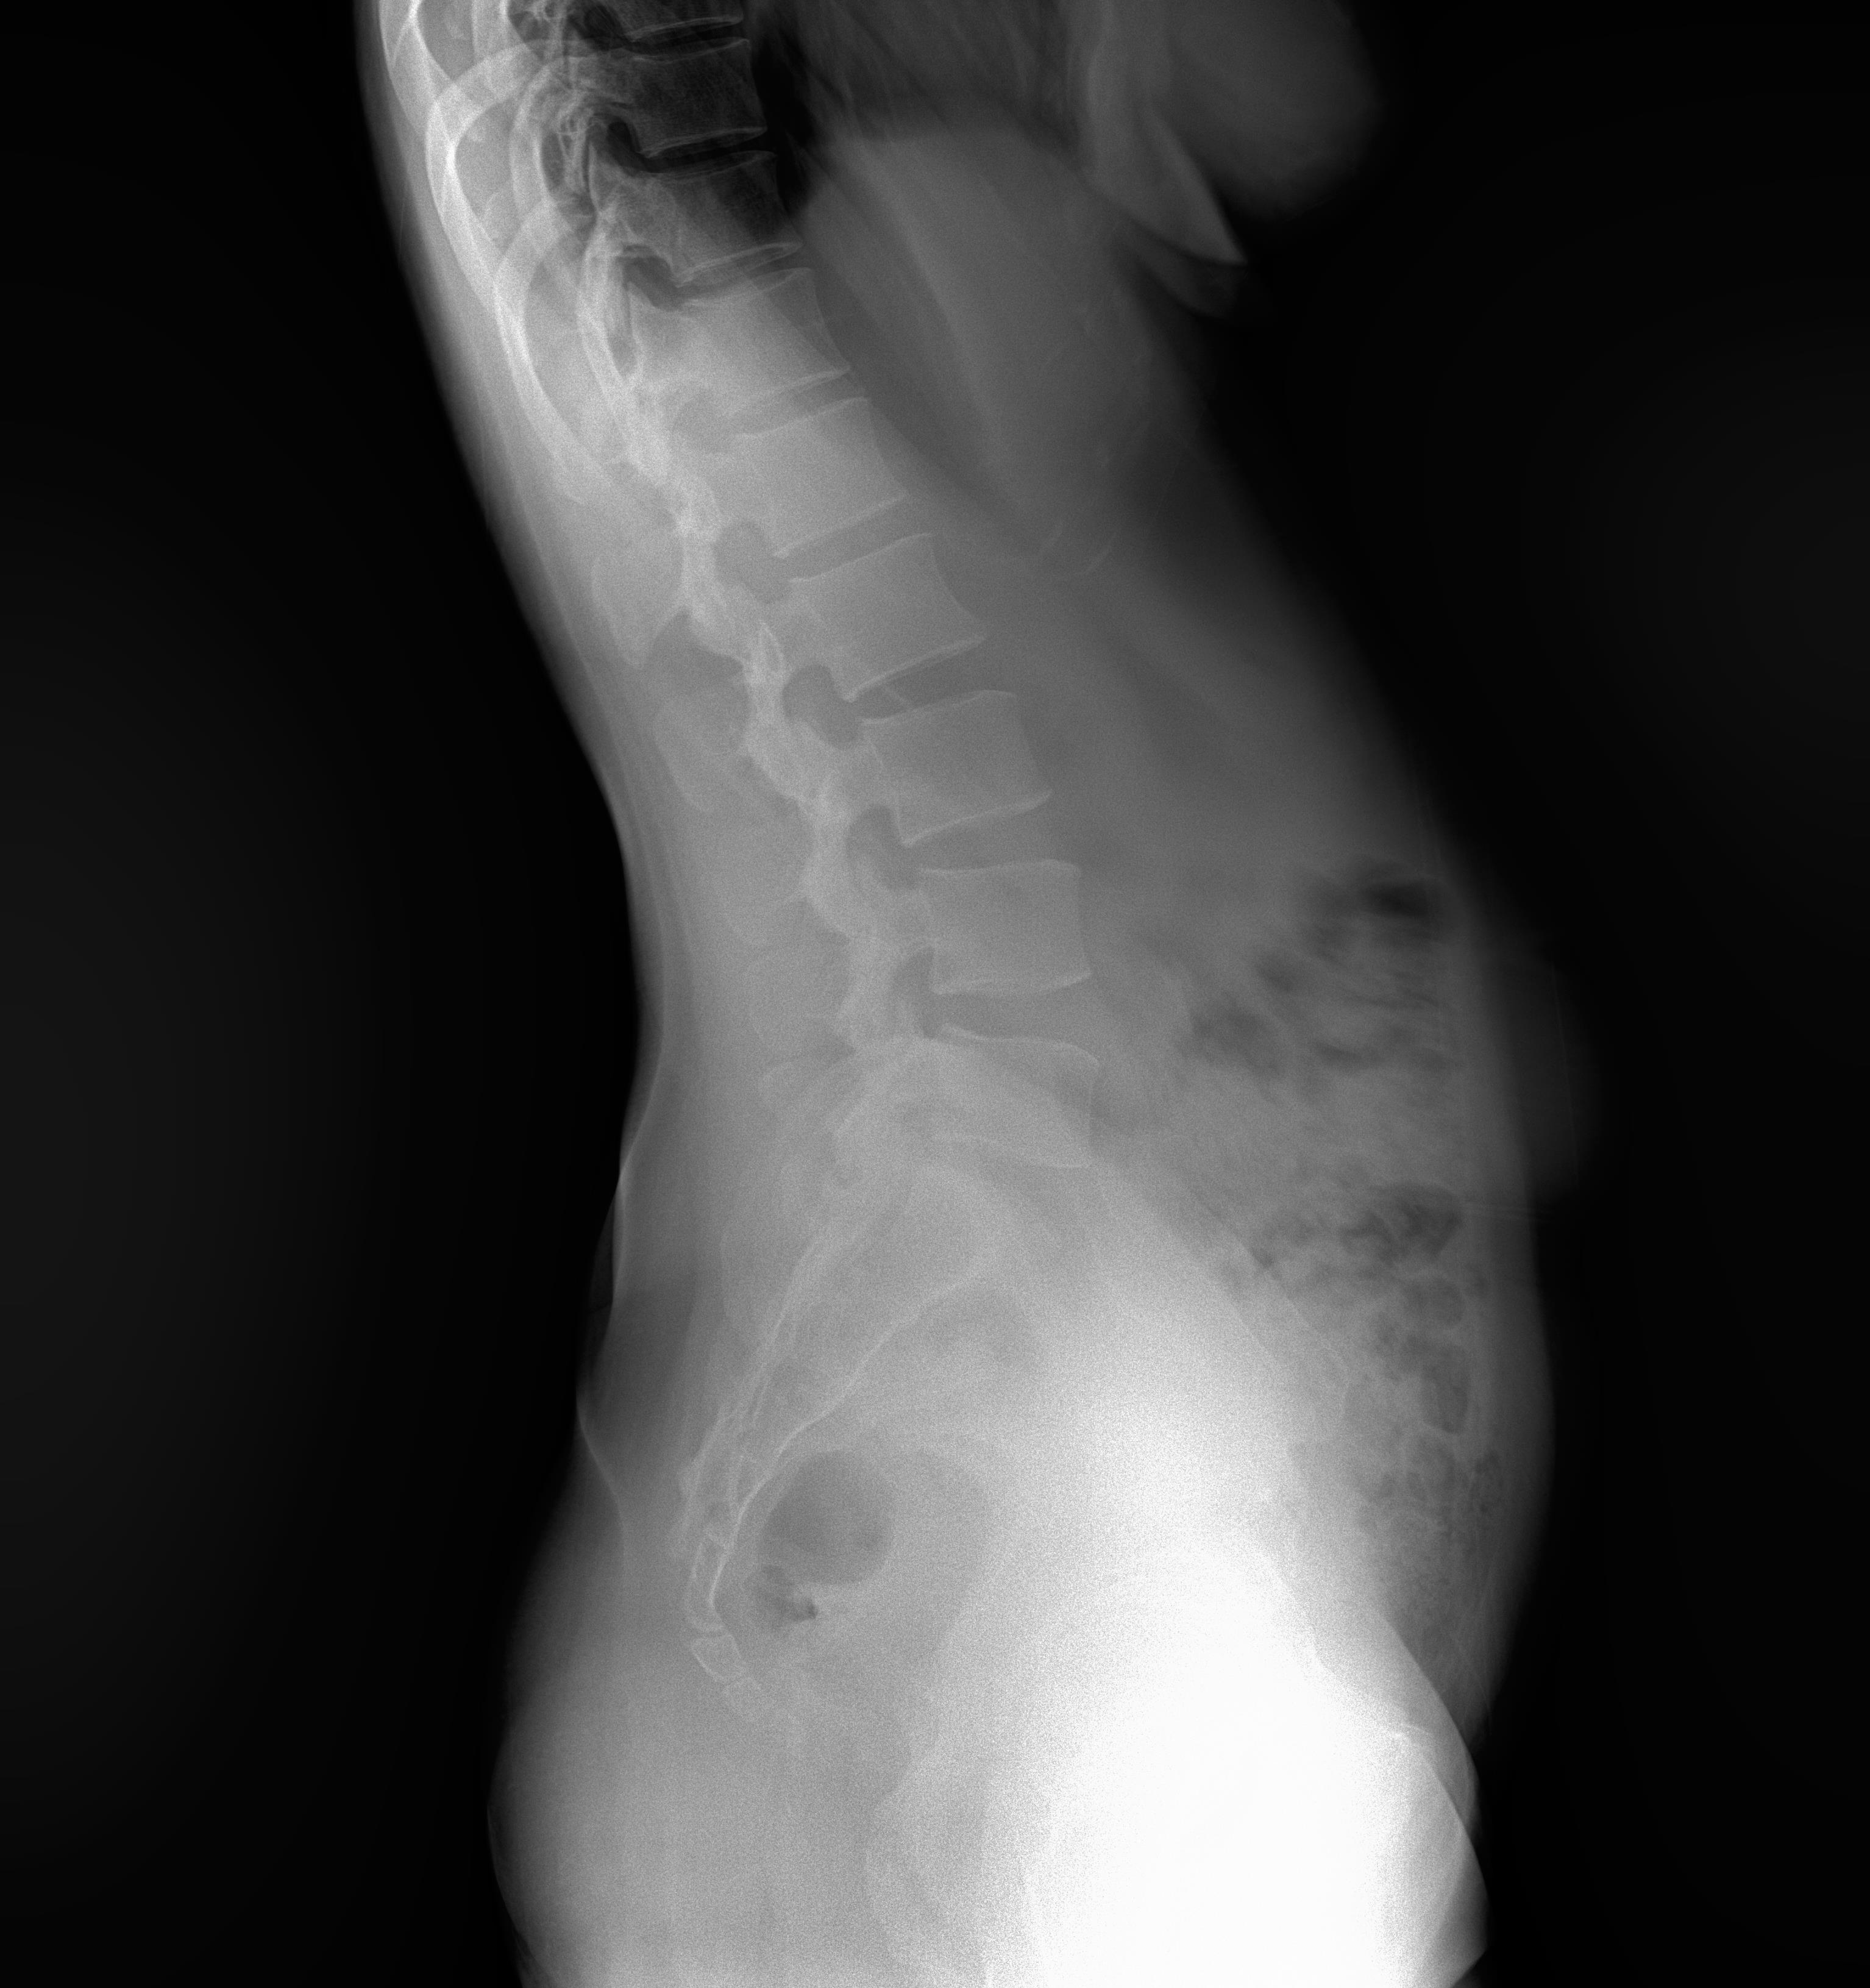

Western Australia, Australia Mar 18, 2021 (Issuewire.com) - Say goodbye to those long waiting times for full spine or leg length studies because within 1 second you can achieve a quick image acquisition with the Longtail – the latest innovative x-ray technology from ATX Medical Solutions. With over 30 years of experience, ATX Solutions has evolved with a profound knowledge of X-ray equipment and its services. The company takes pride in offering a high level of service with unlimited user support to ensure maximum benefits. Recently, a team of experts has initiated the use of this new digital X-ray equipment installed at Capital Radiology in Morley, Western Australia. Clients may ask for the relevance and importance of this newly installed system. Well, to answer their query, Regional Manager at Capital Radiology WA, Joel Scaddan, identified, 3 key features worth mentioning include the following:

So, what does this all mean? In a nutshell, the Longtail digital radiography system delivers the highest image quality, geometric accuracy whilst reducing the amount of radiation with no image overlap received by the patient per diagnostic study. Moreover, practitioners will find it more convenient as they are now able to deliver swift diagnostic results. Managing Director Roger Davis commented the Longtail will supersede existing technologies for full spine imaging systems that are subject to excessive dose, multiple exposures, and software image adjustment techniques that may compromise the diagnosis.